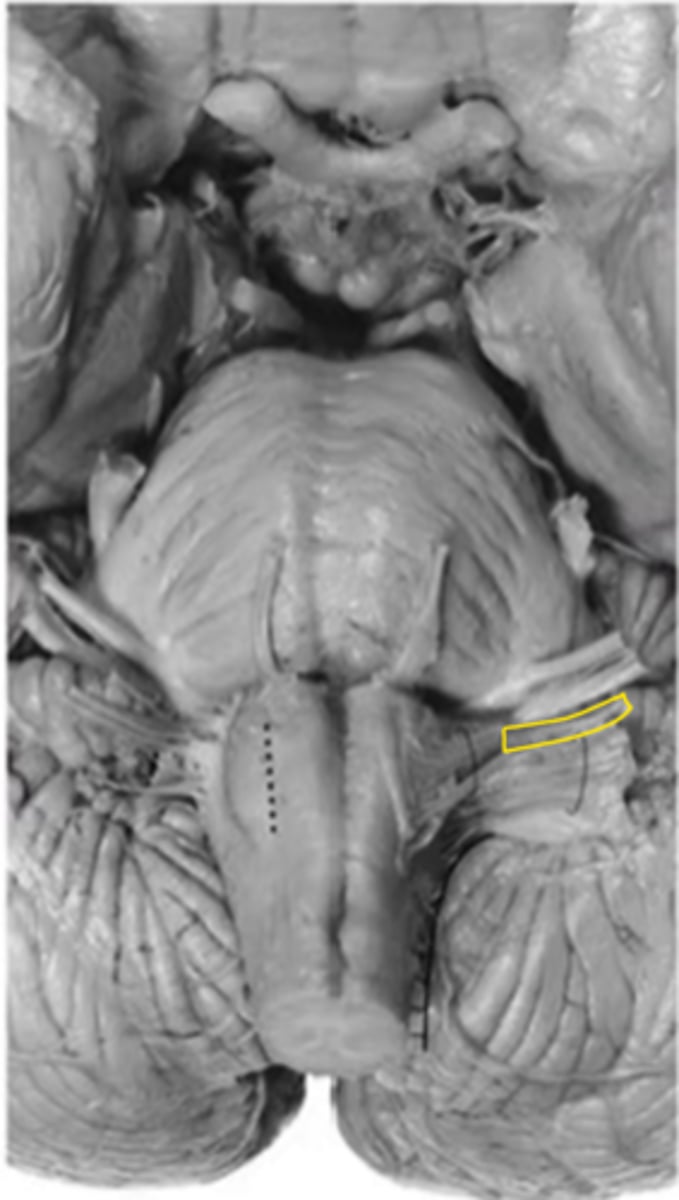

olive

ID the structure

pre-olivary sulcus

hypoglossal nerve

ID the nerve